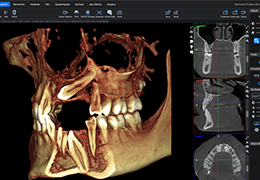

Traditional multi-planar slicing

High-quality and fast 3D reconstruction and 3D rendering

Performs 3D reconstruction and volume rendering.

Multi-planar slicing.

Oblique slicing.